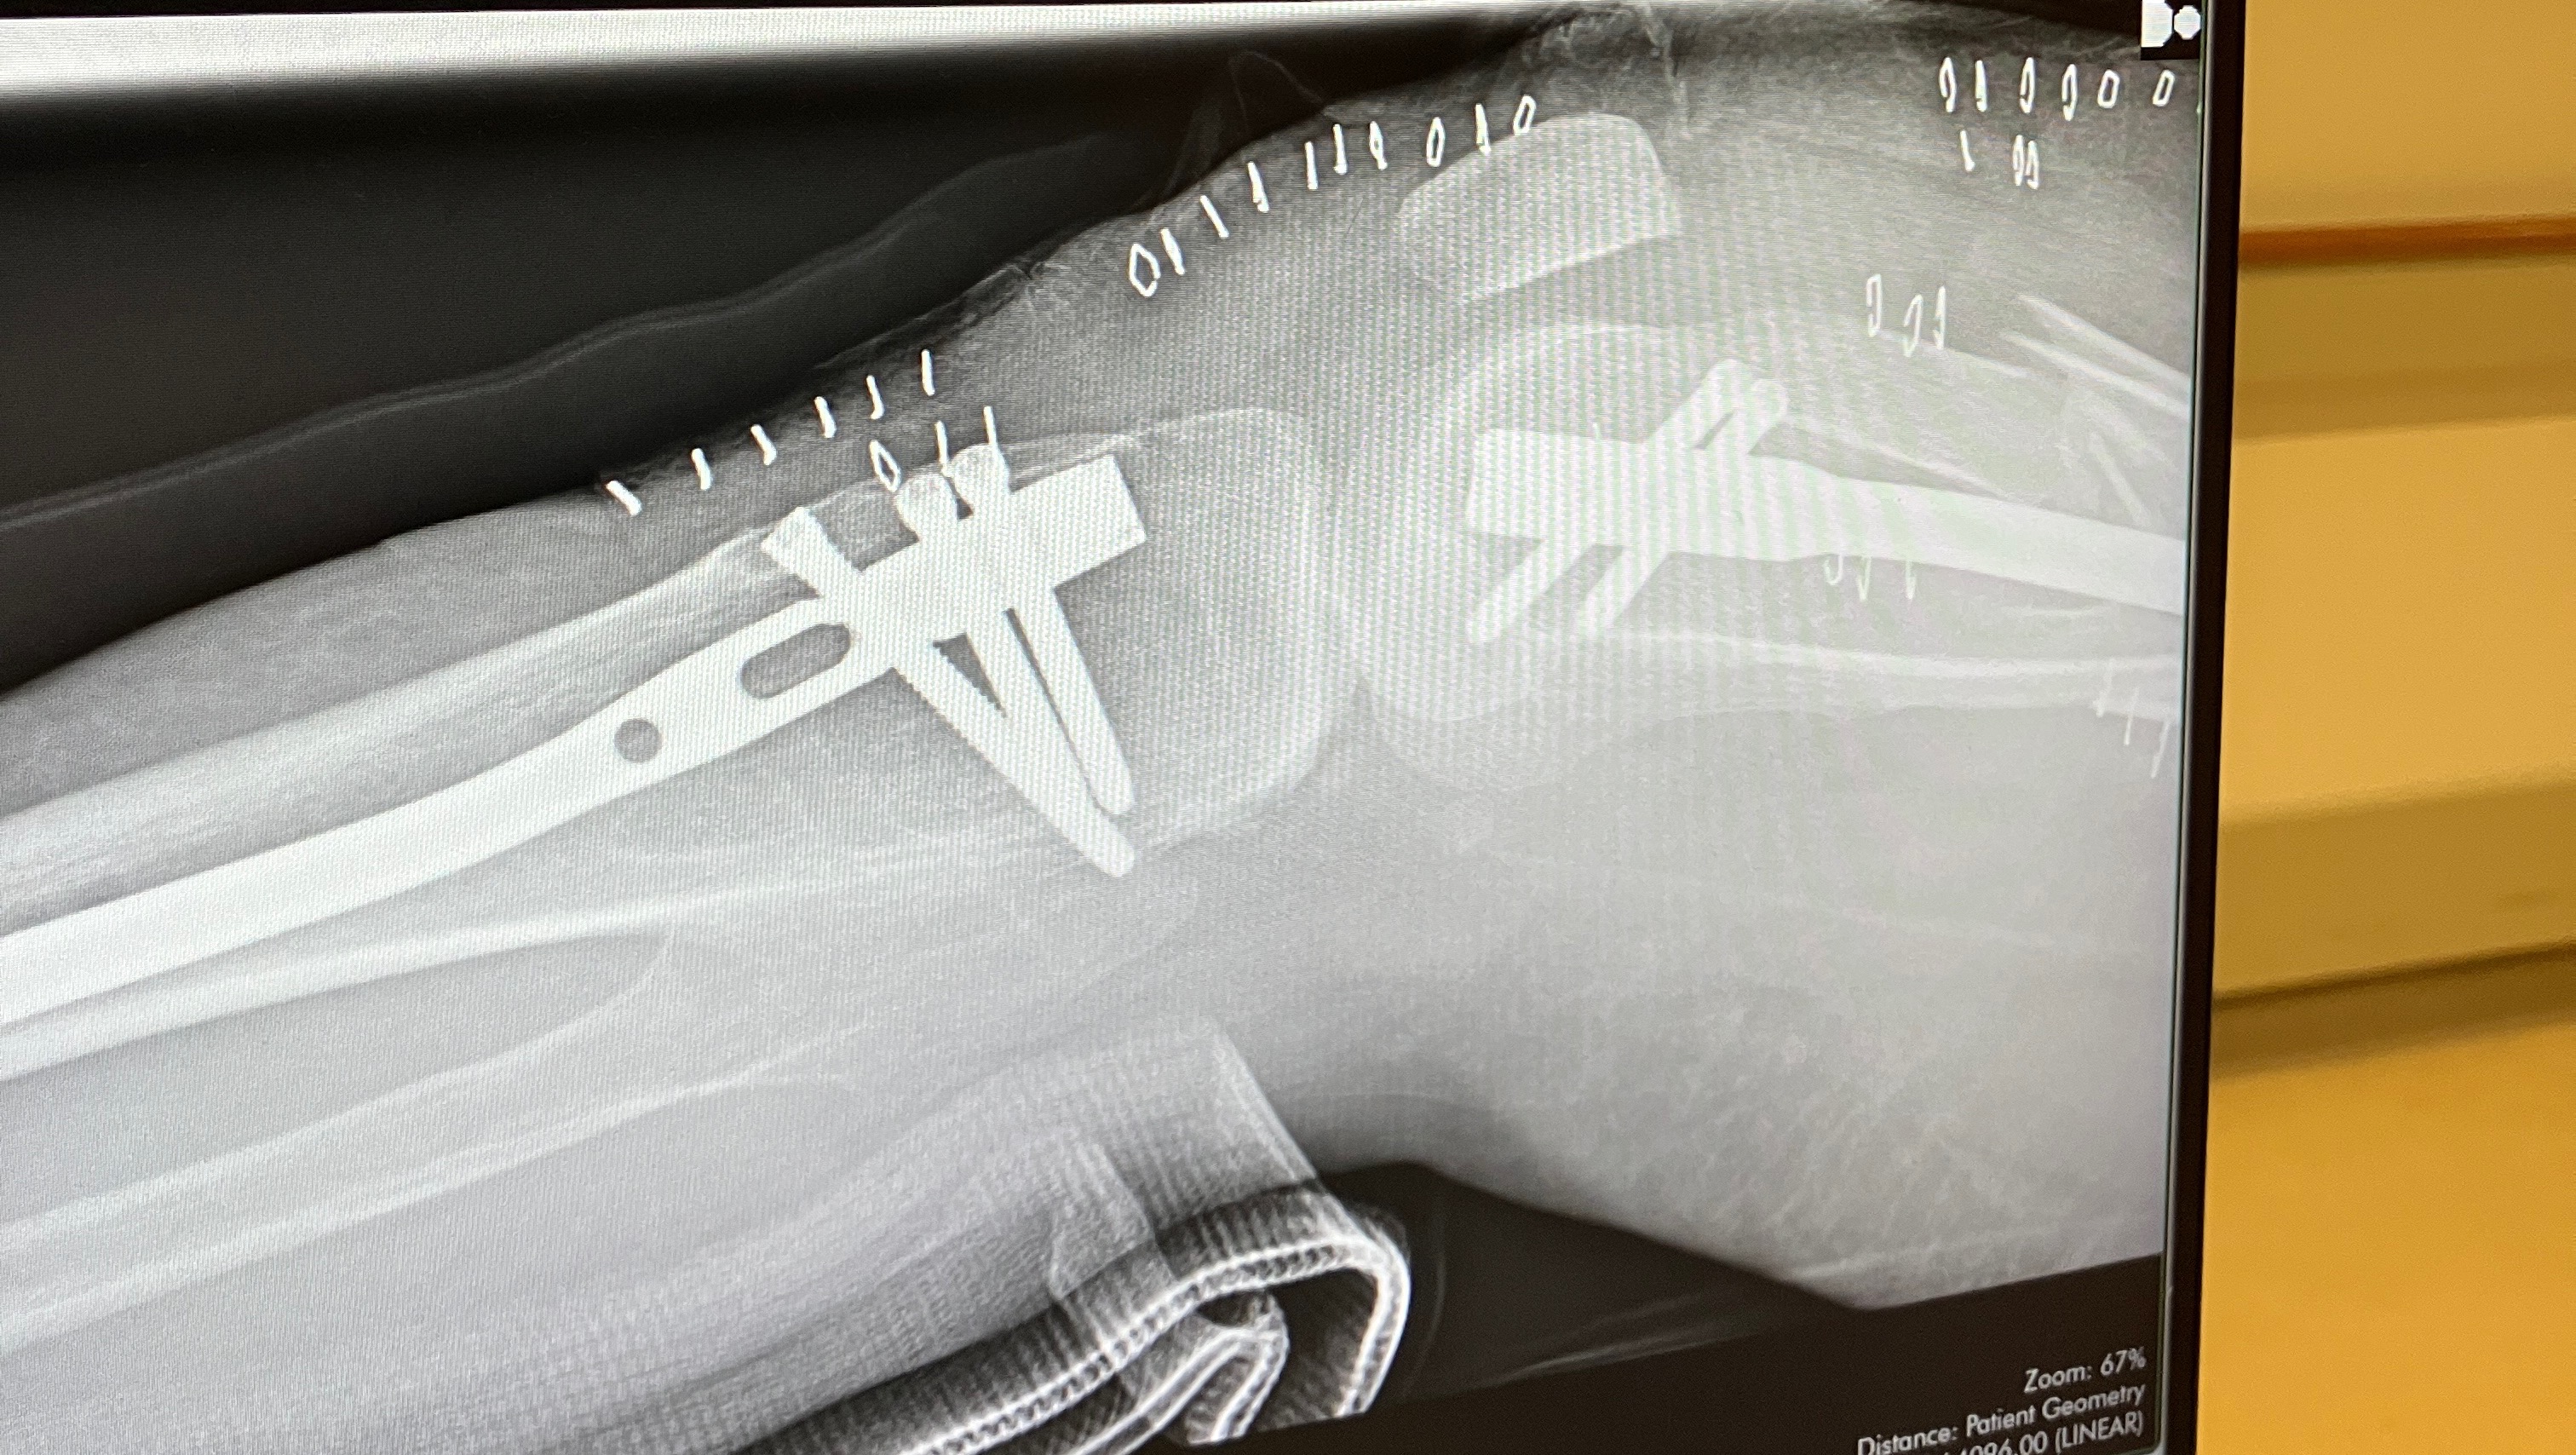

Update- Tony is still fighting his fight! Tony is currently doing oral chemotherapy which is easier on him. He has been able to stay out of the hospital since starting the oral chemotherapy which is amazing news however Lisa is now hospitalized. Two months ago when Lisa was at work she fell and injured her knee. She has been since been off She was finally scheduled for surgery on October 15th! After leaving her pre-op appointment she fell in the waiting room and broke her leg in three different places. She had emergency surgery on her leg that same night. She was just transferred to a rehab facility while she heals. Doctors say she will be out of work for 8 months to a year!